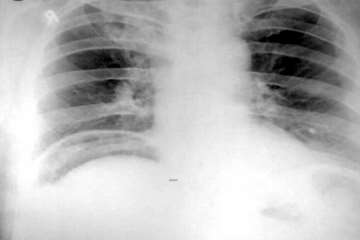

copy.png)